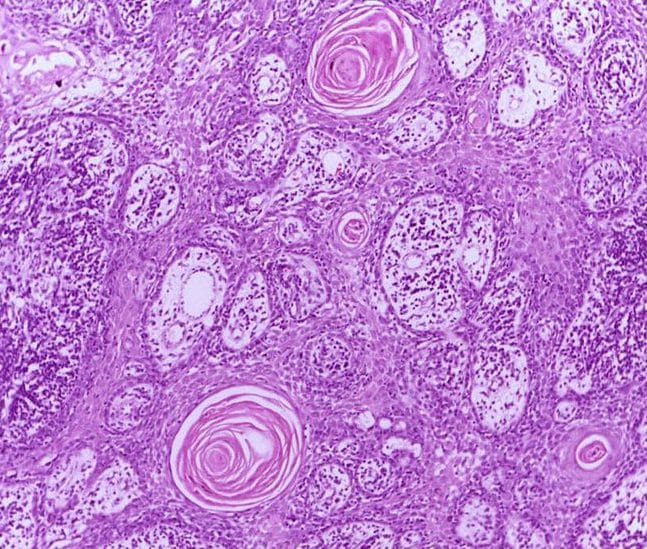

What Does Squamous Cell Carcinoma Look Like Under A Microscope . When examined under the microscope, nkscc is. Are there any features common to all squamous cell carcinomas? They all tend to look similar under a microscope. Sccs can occur anywhere on the skin. That’s how they get classified. What does squamous cell carcinoma look like? How does the squamous cell carcinoma of the skin look? What does nonkeratinizing squamous cell carcinoma look like under the microscope? In people with pale skin, they are most commonly seen on the face, lips, ears, hands,. People with squamous cell carcinoma of the skin have damaged, scaly patches of skin on areas with high uv exposure,. Scc may look like a firm, smooth bump, often with a depression or ulcer in the middle. Most sccs usually look scaly or crusty, raised and rough as they originate from the outer layer of the skin. Sccs can vary in their appearance.

From www.microscopyu.com

Squamous Cell Carcinoma at 20x Magnification Nikon’s MicroscopyU What Does Squamous Cell Carcinoma Look Like Under A Microscope Are there any features common to all squamous cell carcinomas? How does the squamous cell carcinoma of the skin look? Scc may look like a firm, smooth bump, often with a depression or ulcer in the middle. Most sccs usually look scaly or crusty, raised and rough as they originate from the outer layer of the skin. What does squamous. What Does Squamous Cell Carcinoma Look Like Under A Microscope.